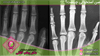

فهرست مقالات سن استخوانی شما چقدر است؟ امروزه یکی از مواردی که به کمک آن سن را ارزیابی میکنند، سن استخوانی است. ۱۵ اَمرداد ۱۳۹۷ رادیولوژی چیست؟ رادیولوژی چیست و چه کاربردهای تشخیصی و درمانی دارد؟ و معرفی انواع دستگاههای آن. ۱۵ اَمرداد ۱۳۹۷ بایگانی مقالات شامل رادیولوژی سونوگرافی بیماری ها پروتز نمونه برداری پستان تروئید MRI پستان ماموگرافی وایرگذاری(2) کالاتوگرافی فیلم های آموزشی سرطان و پیشگیری از آن آپاندیس پانکراس طحال آدرنال پروستات کبد و مجاری صفراوی پستان تیروئید و پاراتیروئید کلیه و مجاری ادراری دانستنی های پزشکی عمومی حاملگی تغذیه و سلامت رحم و تخمدان دانستنی های پزشکی زنان مقالات بایگانی 1401 آبان (1) مهر (4) شهریور (6) اَمرداد (5) تیر (9) خرداد (7) اردیبهشت (7) فروردین (4) بایگانی 1400 اسفند (4) بهمن (2) دی (6) آذر (4) آبان (2) مهر (2) شهریور (5) اَمرداد (4) تیر (1) خرداد (2) اردیبهشت (4) فروردین (2) بایگانی 1399 اسفند (5) بهمن (5) دی (2) آذر (1) آبان (2) مهر (7) شهریور (2) اَمرداد (6) تیر (6) خرداد (6) اردیبهشت (1) بایگانی 1398 بهمن (1) آبان (1) مهر (1) شهریور (1) تیر (2) خرداد (1) اردیبهشت (1) بایگانی 1397 بهمن (1) مهر (1) اَمرداد (2) تیر (38) خرداد (17) اردیبهشت (1)